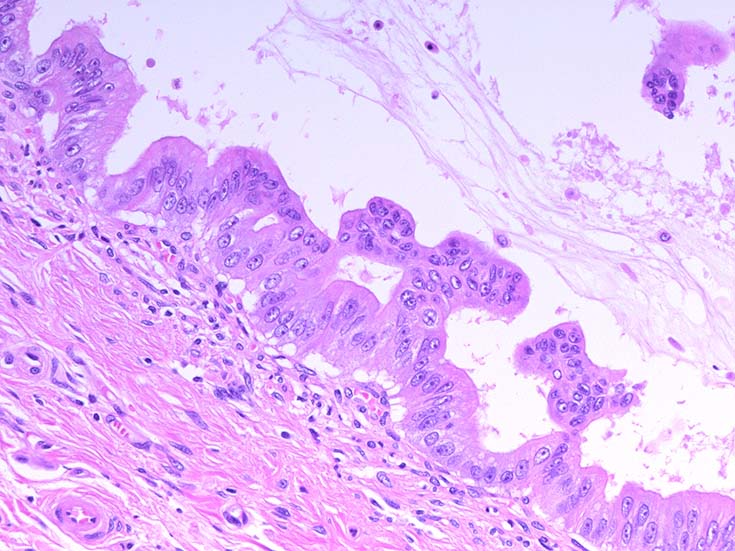

膵上皮内腫瘍性病変 pancreatic intraductal neoplasm(PanIN)*16

Low-grade PanINとhigh-grade PanINの分類

high-grade PanIN

PanINの図譜はJohns Hopkins The Sol Goldman Pancreatic Cancer Research CenterのHome page*19から引用.

2. PanIN-2, PanIN-3;

• TP53の不活化--PanINでのIHCでは機能喪失が,PanIN3のみで観察される. 膵癌発がん過程の遅い段階に出現する事象.

• SMAD4の不活化--PanIN3の30%で発現陰性化. PanIN-1,2では, SMAD4免疫染色は陽性. 発現の陰性化は後期PanINで発現する重要な異常*20.

• BRCA2(DNA修復に重要な遺伝子)の不活化--PanINではPanIN3に特異的なイベント. germ line変異は浸潤性膵管癌の7~10%に認められる.